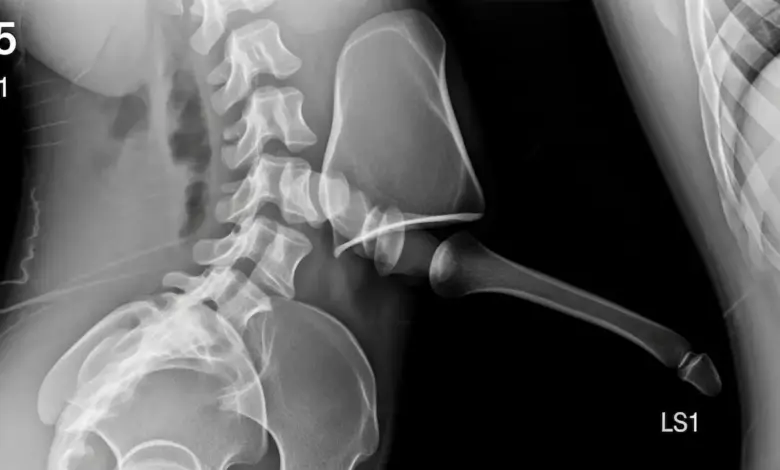

A espondilolistese displásica é um escorregamento congênito entre as vértebras, mais comum em L5 S1. De acordo com a estudo publicado no PubMed.

É um tipo de listese de origem congênita. As facetas articulares nascem orientadas de forma anômala, o arco posterior pode comprimir a cauda equina e a translação entre L5 e S1 tende a ocorrer ao longo do crescimento.

Diferente da forma ístmica, não há obrigatoriamente fratura da pars, o problema está na anatomia que permite o deslizamento.

• Radiografias AP e perfil, com medidas de Meyerding e dos ângulos.

• Radiografias dinâmicas em flexão e extensão, para avaliar a instabilidade.